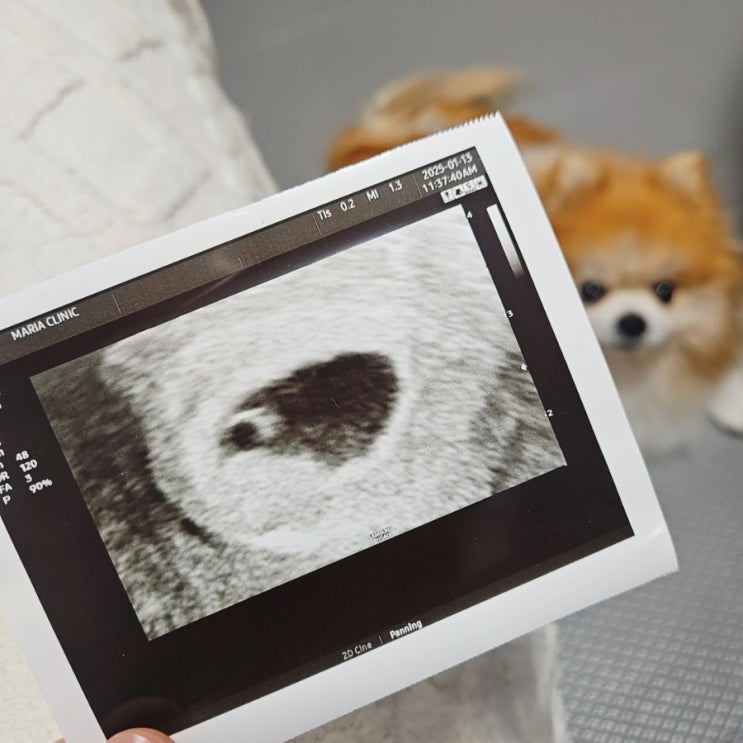

평촌마리아 8주 1일차 초음파, 속쓰림, 구렁이 태몽, 체덧, 변비

평촌마리아 8주 1일차 초음파, 속쓰림, 구렁이 태몽, 체덧, 변비 임신 8주 1일차 평촌마리아로 2주만에 초...